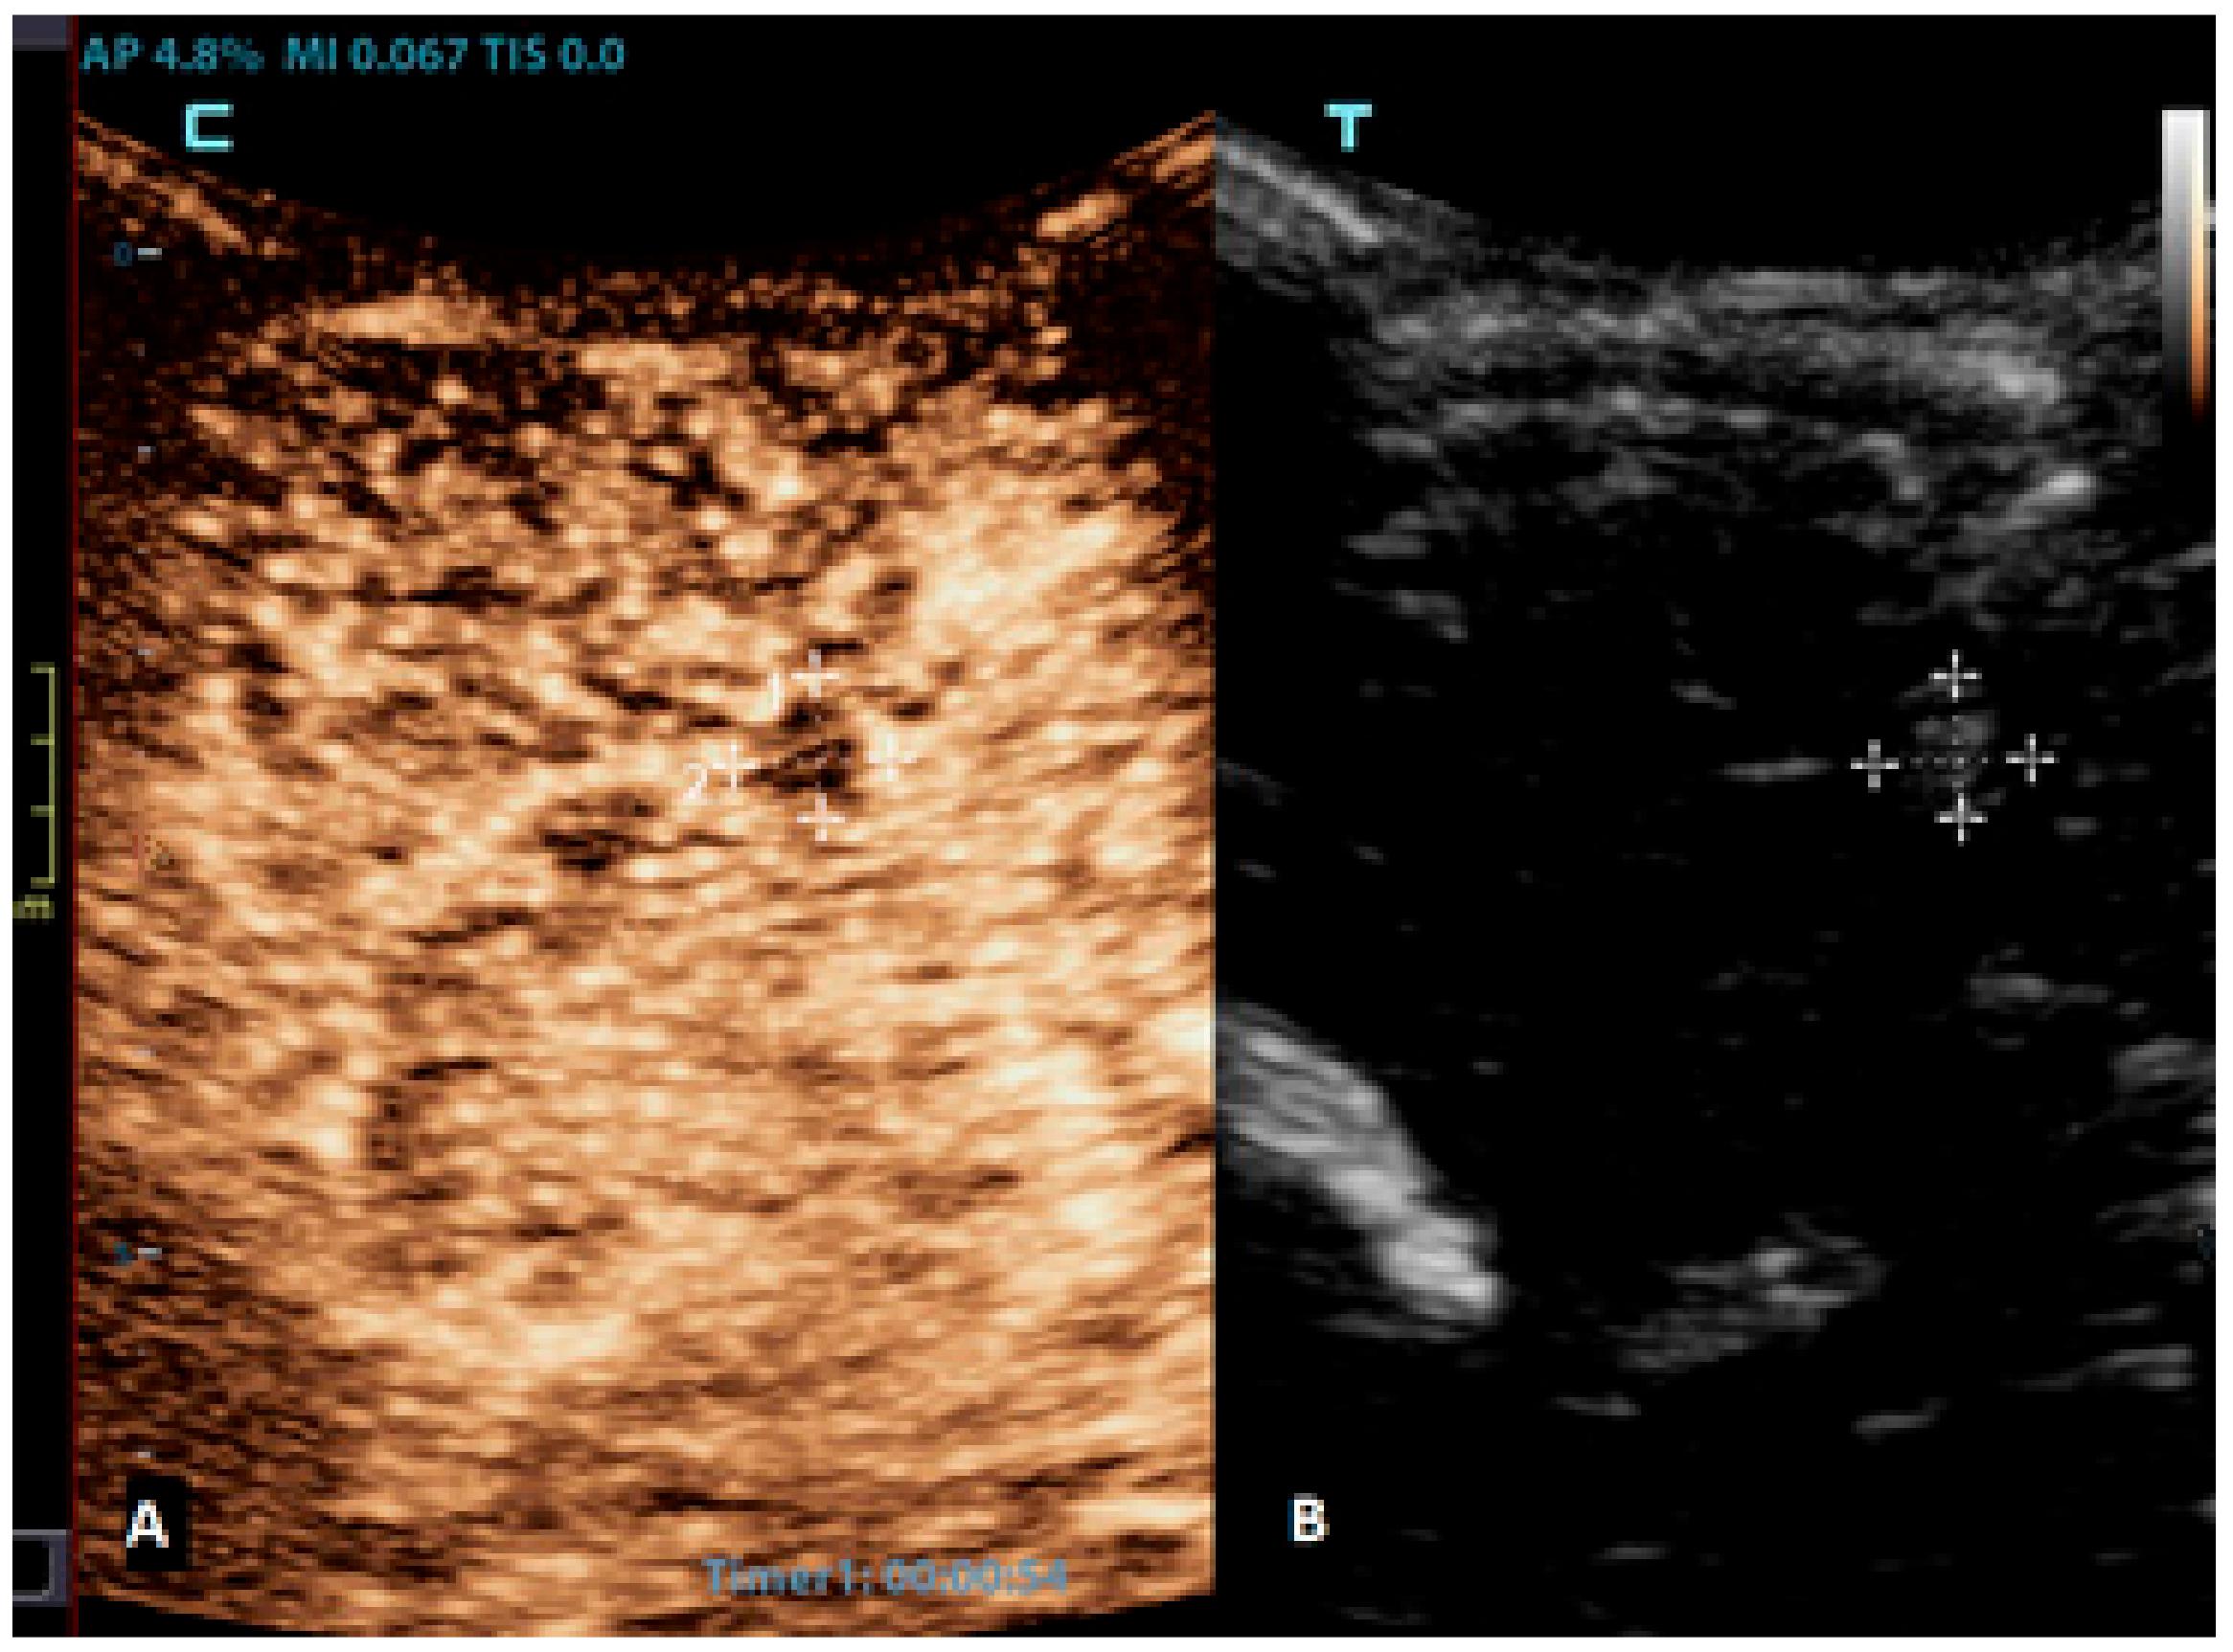

Figure 6.

A 2-month-old boy with acute lymphoblastic leukaemia and candida sepsis. Slowly growing hyperechoic lesions were detected using a brain ultrasound. (A) The sagittal CEUS image of the brain at 54 s after the application of contrast agent shows high signal intensity only at the rim of the lesion (crosses). Candida micro-abscesses were suspected and later confirmed using a brain MRI scan. (B) A sagittal reference grayscale ultrasound image shows a small hyperechoic lesion (plusses).